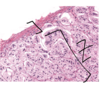

Pig liver -

liver is invested by a connective tissue capsule, Glisson’s capsule (GC), from which in the pig, septa (Se) extend to subdivide the gland into more

or less hexagon-shaped classical lobules (Lo). Blood vessels, lymph vessels, and bile ducts travel within the connective tissue septa to reach the apices of the classic lobules, which are known as the portal area (PA). Bile reaches the portal area from within the lobules, whereas blood enters the substance of the lobules from the portal areas. Within each lobule, the blood flows through tortuous channels, the liver sinusoids, to enter the central vein (CV) in the middle of the classical lobule.

Classical liver lobule - classical liver lobule (outlined by arrowheads) is defined by the arrangement of connective tissue in the portal tract (B) areas and has its centre at the central vein (A) or terminal hepatic venule. Hepatocytes radiate along blood sinusoids from the tracts to the central vein and bile flows in the opposite direction